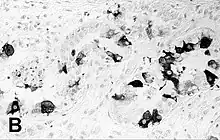

| Immunohistochemical staining of the lung of a seal with PDV infection | |